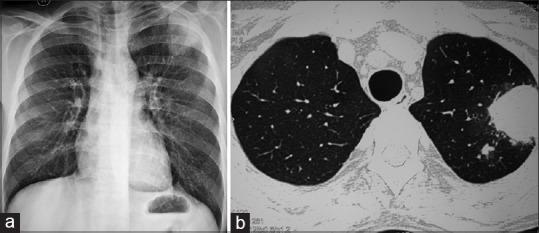

The median age of the study subjects was 54 years (range, 16-76) and majority of them (75%) were males. The risk factors for pulmonary nocardiosis identified in our study were long-term steroid use (55.6%), chronic lung disease (52.8%), diabetes (27.8%), and solid-organ transplantation (22.2%). All the patients were symptomatic, and the most common symptoms were cough (91.7%), fever (78%), and expectoration (72%). Almost two-third of the patients were initially misdiagnosed and the alternative diagnosis included pulmonary tuberculosis (n = 7), community-acquired pneumonia (n = 5), lung abscess (n = 4), invasive fungal infection (n = 3), lung cancer (n = 2), and Wegener's granulomatosis (n = 2). The most common radiographic features were consolidation (77.8%) and nodules (56%). The mortality rate for indoor patients was 33% despite treatment. Higher mortality rate was observed among those who had brain abscess (100.0%), HIV positivity (100%), need for mechanical ventilation (87.5%), solid-organ transplantation (50%), and elderly (age > 60 years) patients (43%).

结果